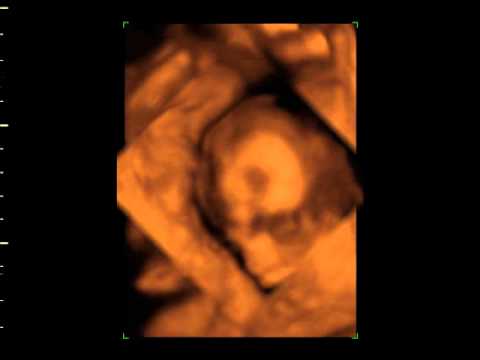

The reconstruction have been acquired 3 1/2 months before birth by means of 3D ultrasound. To the right, one can see a photograph of the baby 24 hours after birth. Jos Stam, University of Toronto. This image shows four frames from an animation of a fire with smoke. ... Fetch This Document